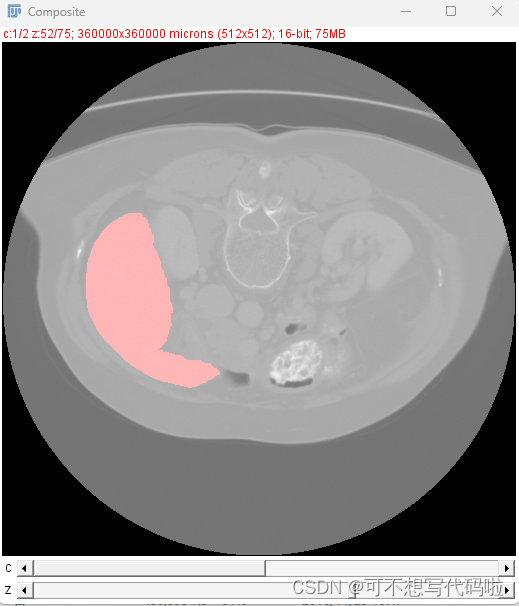

也可以一并显示分割结果。分别打开原数据和分割结果,然后选择Image->Color->Merge Channels,做如下设置,其中分割结果随便选择一个合适的颜色都行,我选的是红色。如果希望还能分别查看原图和分割结果,可以勾选Keep source images。

然后就能看到如下结果。